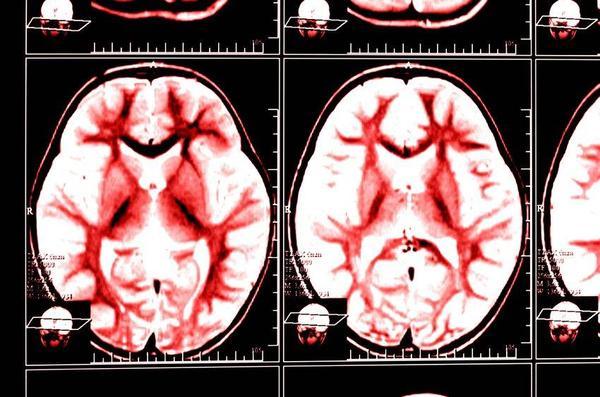

据相关数据统计发现脑梗的死亡率要远远大于癌症,而我国脑梗的发病率占全球总量的1/3,是脑梗重发的国家,每年大概有551万人患上脑梗,所以我国公民对于脑梗应该引起足够的重视。

脑梗需要早发现早治疗,及时治疗还是能够避免其恶化,但若是一旦延误治疗,尤其突然发病就极有可能导致偏瘫和死亡。